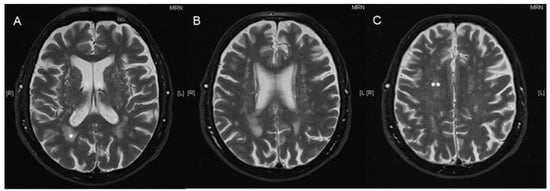

The Fazekas total score is a sum of the PVWM score and the DWM score (Fazekas total score = PVWM + DWM). Figure 1 demonstrates a representative T2 weighted cerebral MRI scan of an 87-year-old male patient with the marked Fazekas score.

Figure 1.

Exemplary MRI scan with annotated Fazekas score. Axial, T2 weighted cerebral MRI scan of an 87-year-old male patient before cochlear implantation with a Fazekas total score of 5, one asterisk indicates periventricular white matter lesions (PVWM *) score of 2; two asterisks indicate deep white matter lesions (DWM **) score of 3 (axial, A–C).